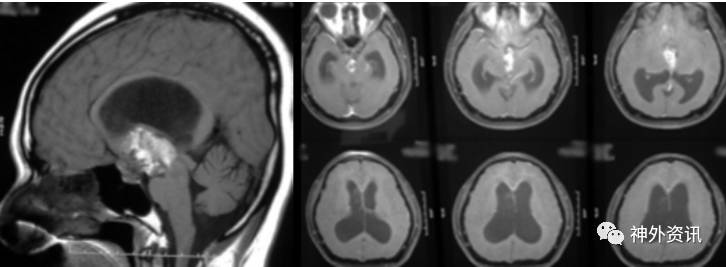

术后复查MRI显示肿瘤次全切,垂体柄保护完整,脑室结构复位满意(图5)。随访6个月,肿瘤无进展和神经系统症状未恶化。

图5. 术后MRI显示肿瘤次全切除。